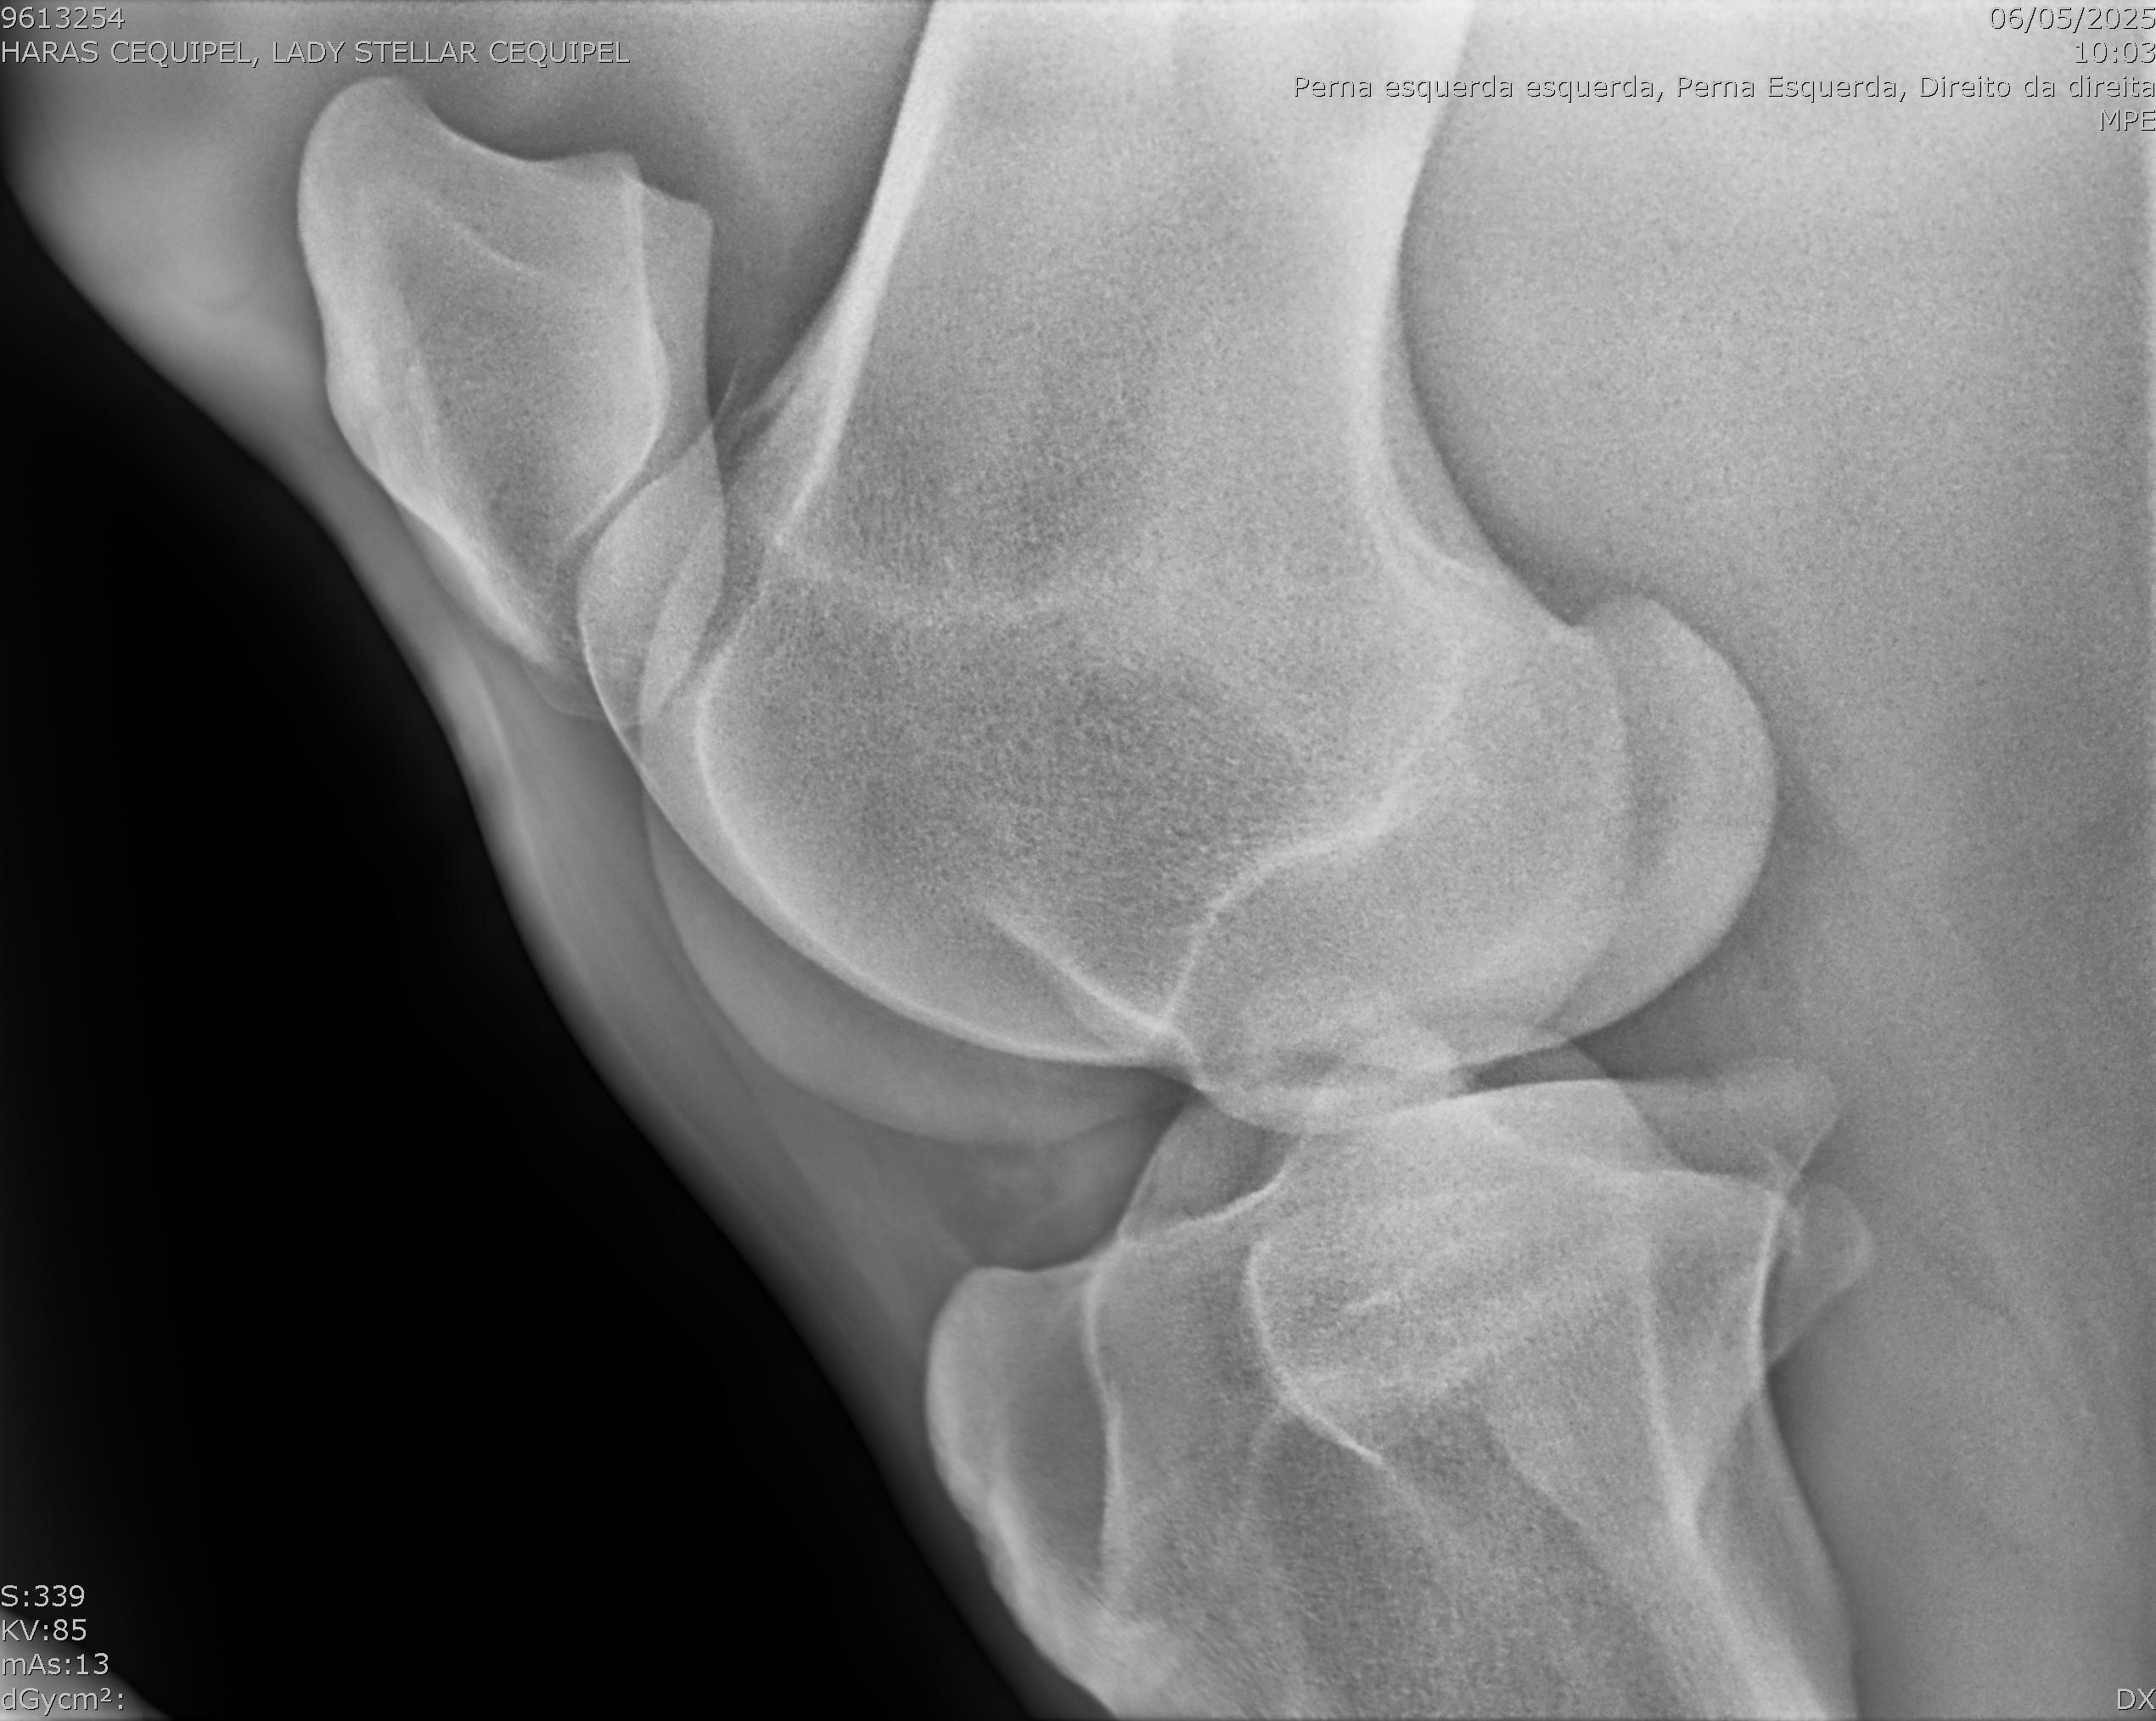

:: RAIOS-X DO LOTE